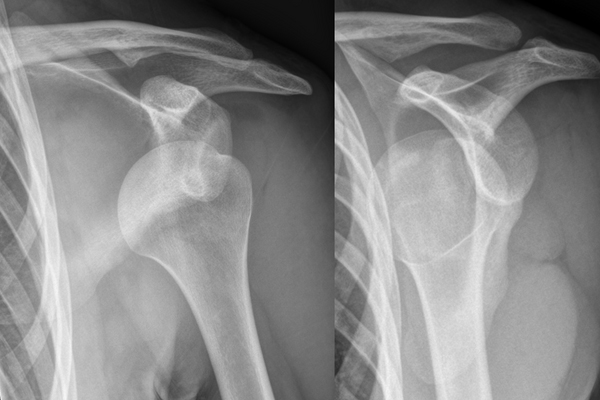

SHOULDER FRACTURES